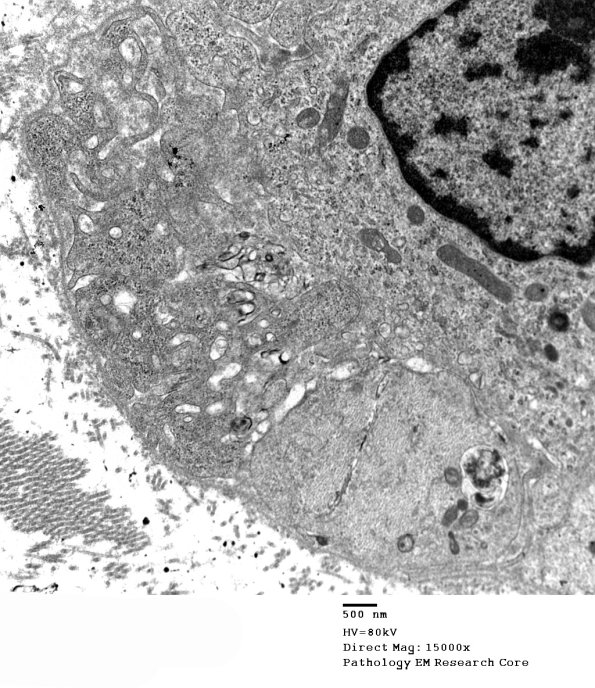

A demyelinated axon with an intra-Schwann cell adjacent macrophage with numerous pseudopods. Notice the adjacent endoneurial macrophage. (electron micrograph)